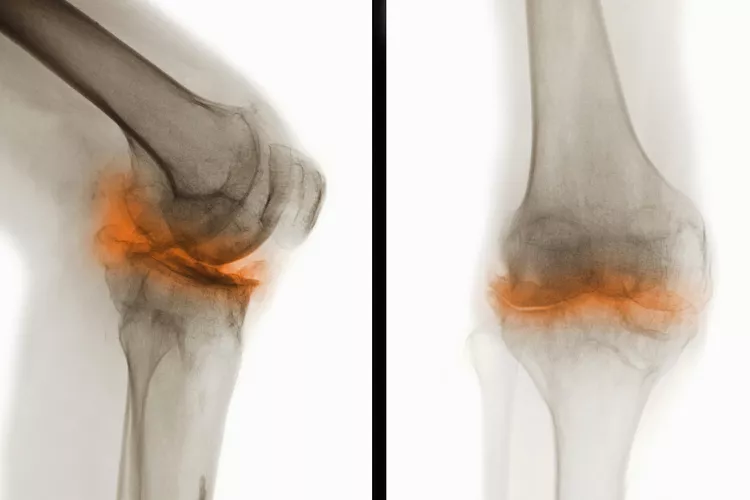

骨關(guān)節(jié)炎(Osteoarthritis, OA),一種常見(jiàn)的慢性關(guān)節(jié)疾病,主要特征是關(guān)節(jié)軟骨退化和關(guān)節(jié)邊緣骨質(zhì)增生。隨著病情進(jìn)展,骨關(guān)節(jié)炎不僅會(huì)導(dǎo)致關(guān)節(jié)疼痛和功能受限,還可能引發(fā)一系列并發(fā)癥,影響患者的整體健康和生活質(zhì)量。

在骨關(guān)節(jié)炎(OA) 中,覆蓋骨頭末端并幫助骨頭相互滑動(dòng)的光滑軟骨會(huì)逐漸磨損。這會(huì)導(dǎo)致骨頭相互摩擦和磨擦。

關(guān)節(jié)損傷

可能的問(wèn)題包括:

- 脊柱神經(jīng)受到擠壓(后天性脊椎滑脫或脊椎狹窄)

- 關(guān)節(jié)感染,但這種情況很少見(jiàn)

- 關(guān)節(jié)周?chē)募‰旌晚g帶變薄或撕裂,導(dǎo)致關(guān)節(jié)不穩(wěn)定

- 軟骨溶解癥,軟骨突然完全破裂,導(dǎo)致關(guān)節(jié)內(nèi)組織松散

- 應(yīng)力性骨折,由于反復(fù)的壓力而緩慢地在骨頭上形成細(xì)微裂縫

- 貝克囊腫是膝蓋后面的軟性充滿(mǎn)液體的腫塊。它們大多無(wú)痛,但會(huì)壓迫血管導(dǎo)致腿部腫脹,或破裂并引起疼痛